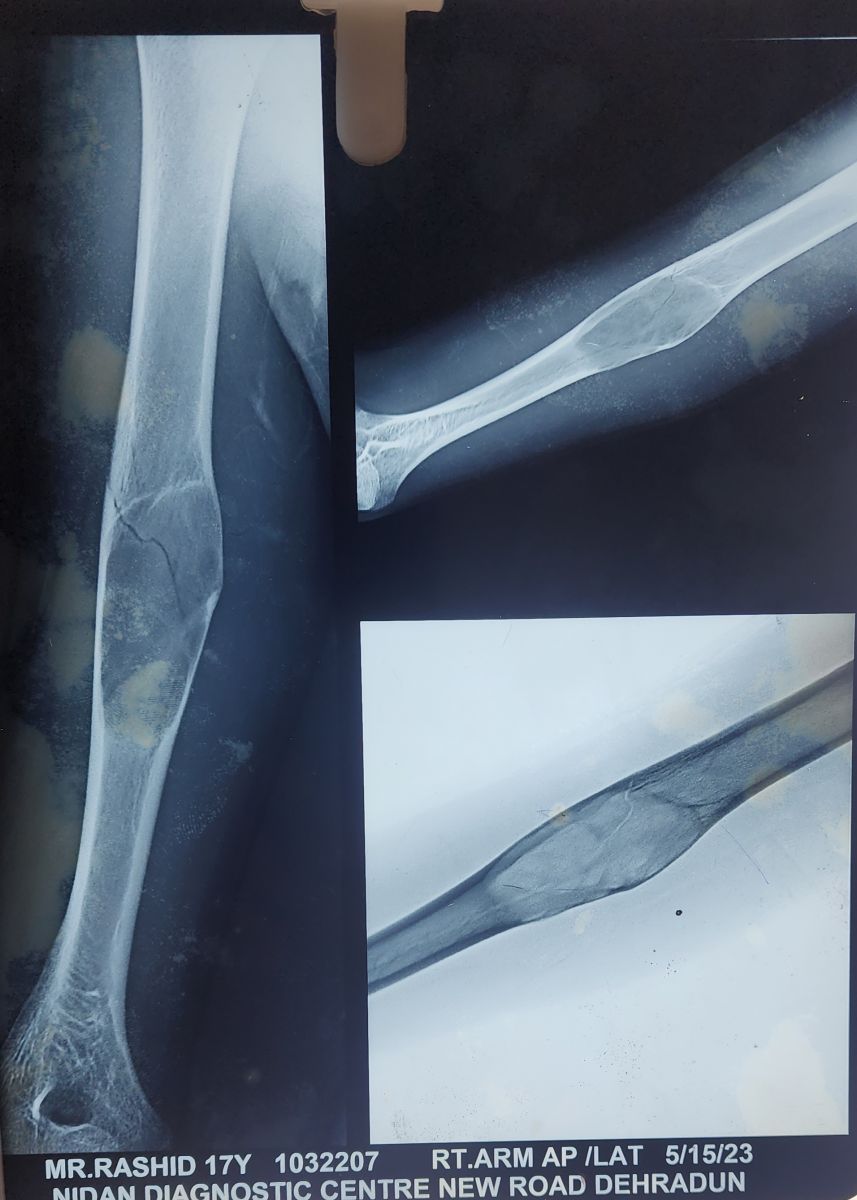

Radiographic imaging revealed an osteolytic lesion with cortical destruction in the proximal diaphysis of the right humerus associated with a pathological fracture.

Magnetic resonance imaging (MRI) depicted a expansile altered signal intensity lesion with endosteal scalloping, cortical thinning and a narrow zone of transition involving mid-diaphyseal region. Cortical defect was visualised along with adjacent soft tissue edema.

Figure 1: Preop xray of the patient showing a expansile lytic lesion in humerus diaphysis with pathological fracture.

Figure 2: Pre-op MRI showing expansile lytic lesion in the mid humerus with altered signal intensity and cortical breach.